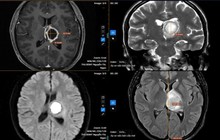

Kết quả khám lâm sàng và chiếu chụp cần thiết cho thấy người bệnh bị hoại tử chỏm xương đùi bên trái, trên nền bệnh xương hóa đá.

Bệnh nhân mắc căn bệnh xương hoá đá.

ThS.BS Nguyễn Đình Hiếu – Phó trưởng khoa Phẫu thuật chấn thương chỉnh hình và y học thể thao - cho biết xương hoá đá (Osteopetrosis hay Marble Bone) – là một rối loạn di truyền cực kỳ nguy hiểm, biểu hiện ở nhiều hệ cơ quan, trong đó có hệ vận động, đặc trưng bởi sự tăng mật độ xương quá mức dẫn đến tình trạng xương rất cứng nhưng lại giòn và dễ gãy.

Riêng ở xương, căn bệnh này đặc trưng bởi sự bất hoạt của tế bào hủy xương (osteoclast) dẫn đến việc mất cân bằng giữa 2 quá trình tạo xương và hủy xương, làm tăng mật độ xương và giảm độ đàn hồi của xương. Người mắc căn bệnh này thường gặp những biến chứng nặng nề và chưa có phương pháp điều trị đặc hiệu, bác sĩ Hiếu nói.